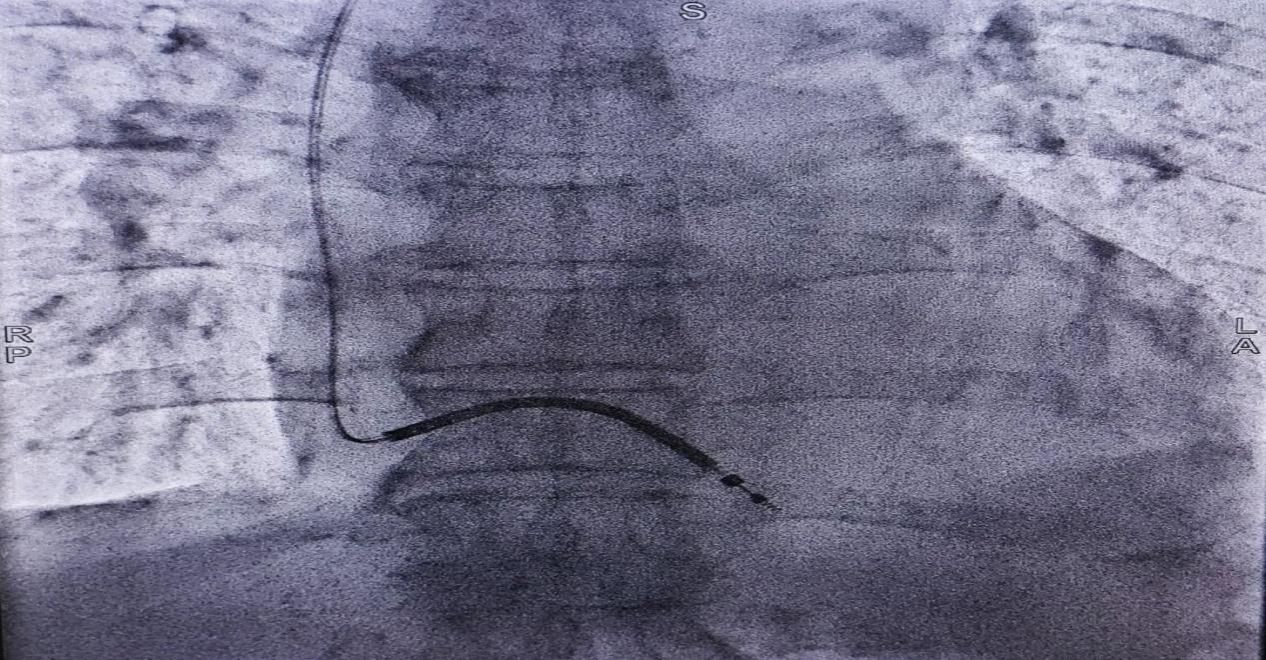

7、新疆医院介入诊疗中心启动运行

近日,心血管内科成功完成首例植入式心脏转复除颤器(ICD)植入手术,成功为一名III度房室传导阻滞的82岁高龄患者,实施首例无导线起搏器植入术(Micra AV型)。消化内科驻疆专家万晓龙教授成功开展首例内镜下逆行胰胆管造影(ERCP)胆总管取石术,标志着医院内镜诊疗水平迈上新台阶。

高难度介入诊疗技术的成功开展,标志着新疆医院介入诊疗中心进入快速发展轨道,助力国家区中高质量发展。